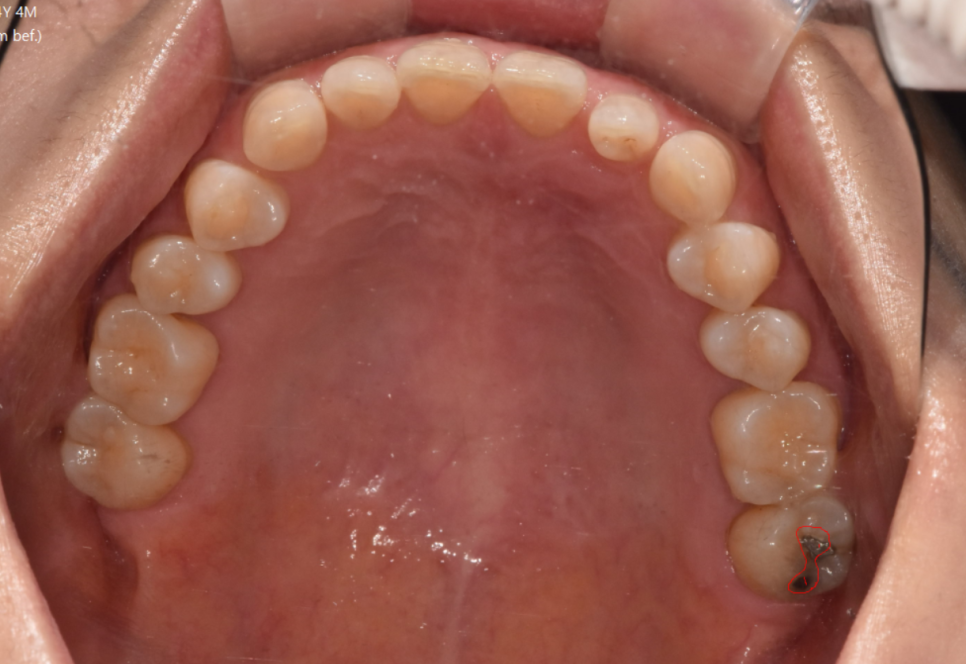

서울바르디치과에서는

최대한 자세히 알려드리기 위하여

사진을 찍어서 설명드립니다.

언제든지 사진이 필요하시면

말씀해주세요!!